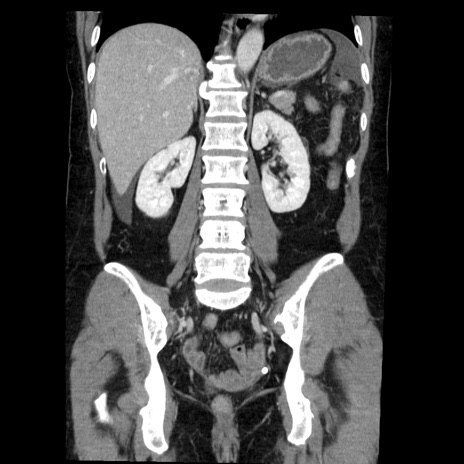

矢状断像

【症例】50歳代女性

【主訴】下腹部痛

【現病歴】本日朝より下痢2回あり。 昼食を食べた後、嘔吐3回、下腹部痛認め、症状軽快せず、当院救急搬送。

最終食事:本日昼(生ものなし)。 昨日の夜、刺身を食ぺたとのこと。周囲に同様の症状の者なし。普段、排便は毎日あるとのこと。

【既往歴】卵巣癌術後(8年前に当院で卵巣摘出)

【身体所見】 意識清明、腹部:平坦、腸蠕動音→、やや硬、下腹部自発痛・圧痛あり、反跳痛あり、筋性防御なし。

【データ】WBC 16000、CRP 0.01